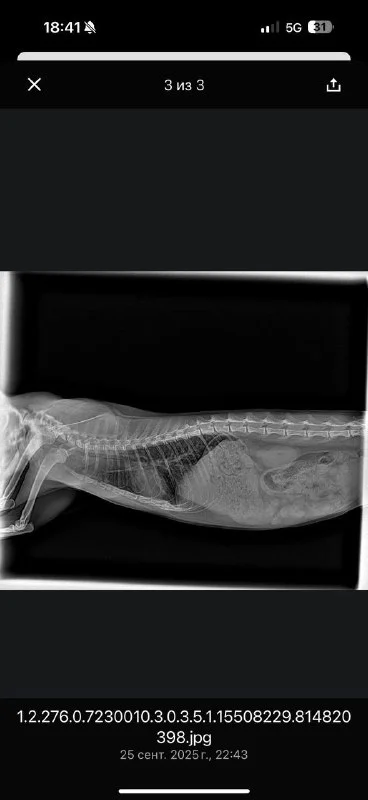

Вчера я ее забрала домой, операция прошла успешно, она уже пытается вставать на все 4 лапы, но у нее действительно есть проблемы с головой, непонятно что со зрением и двигается она только вокруг своей оси, ну ладно с этим потом буду разбираться. Публикую наконец фото рентгена, новый счет (который финально оказался меньше!) ресит с указанием оплаты и баланса.

Рентген ужас,руки в кадре, укладка жуть

Рентген это тот что в имерженси делали это мои руки 🤦🏼♀️ у них бардак конечно, хорошие люди, Михалис хороший хирург, но всегда толпа народа все носятся, но я к ним продолжаю ходить они меня знают и живу рядом